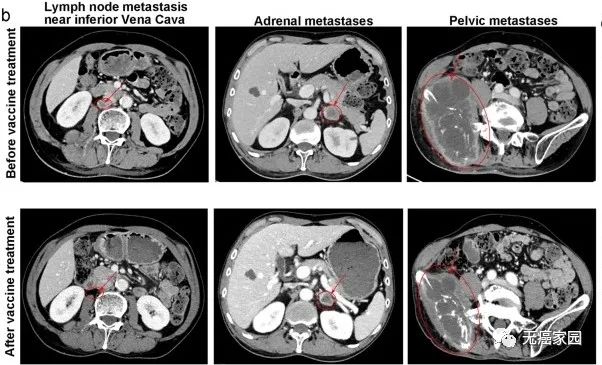

结果显示,12名患者中,3名患者的肿瘤明显缩小,6名患者肿瘤保持稳定,疾病控制率达75%,疗效维持最长的患者已经2年。

图中患者靠近下腔静脉的转移瘤基本消失,肾上腺转移及盆腔巨大转移灶明显缩小对于复发性晚期癌症患者,这种联合疗法可以发挥抗肿瘤的作用,而且不会增加毒性及副作用。Deo-DCVac疫苗是安全和有效的,并适用于晚期肺癌患者。